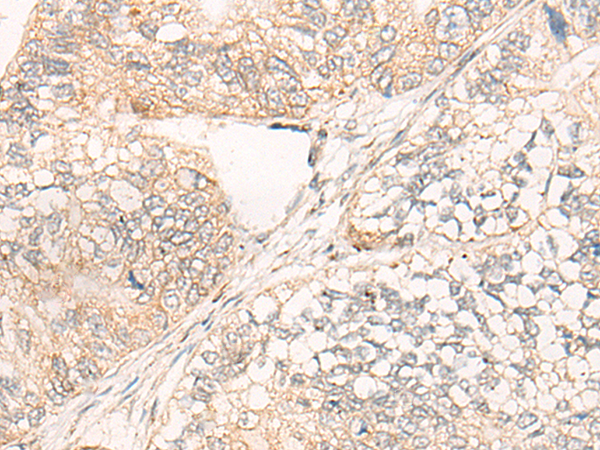

IHC positive control: |

Human gastric cancer |

IHC Recommend dilution: |

20-100 |